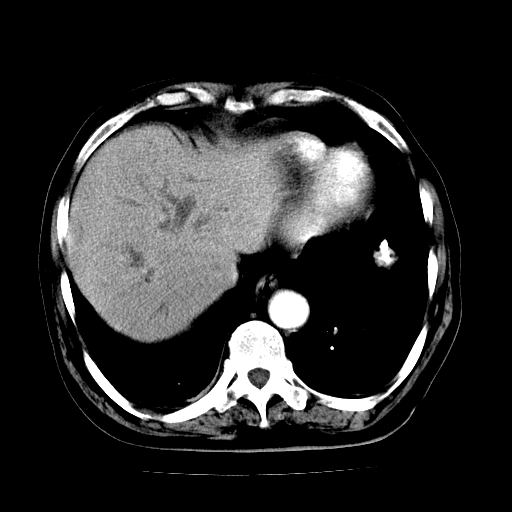

男,71岁,皮肤黄染四天。

肝内外胆管及胆总管上段扩张,考虑为梗阻所致,建议mrcp检查。

支持考虑胆总管癌并肝内外胆管扩张。 局部应薄扫。心包钙化。

胰腺上端胆总管内见软组织影,强化不明显,结合临床,还是考虑低位梗阻性黄疸,胆总管癌可能性大